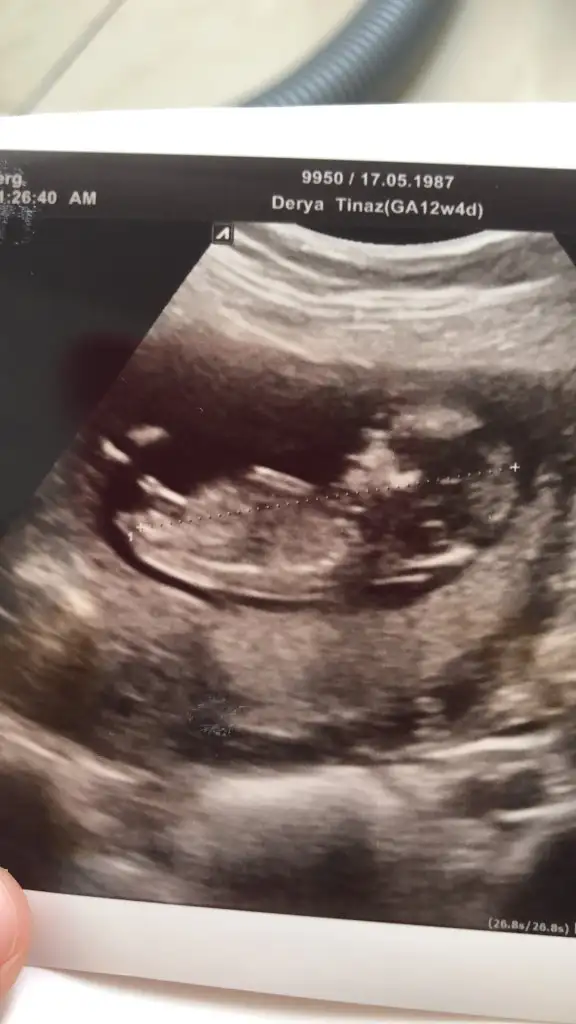

Usgniz 9 haftalık ve nub olmaz 11 yada 12 hafta olmalı o haftalarda tekrar paylaşırsınızAyy heyecanlandım:) nerden anladınız :)

Usg kaç haftalık ve usg karanlık çözemedim başka usg paylaşınIkra meyra kaç haftalığa kadar nub bakıyosunuz kız demiştiniz ama net değildi bide buna bakar mısınız

Yok hiç vajinal değil hepsi karından neyse iki hafta sonra tekrar atarım ozaman yinede sağolasınız ama karından erkek diyorsunuz öylemii6 haftalık usg vajinalsa kız karından bakıldıysa erkek nub için 11 yada 12 hafta olmalı

Evet karından erkek tabi 11 yada 12 hafta usg nub için paylaşırsınız nub dogrulugu dogru tabi usg netse pozisyon uygunsaYok hiç vajinal değil hepsi karından neyse iki hafta sonra tekrar atarım ozaman yinede sağolasınız ama karından erkek diyorsunuz öylemii